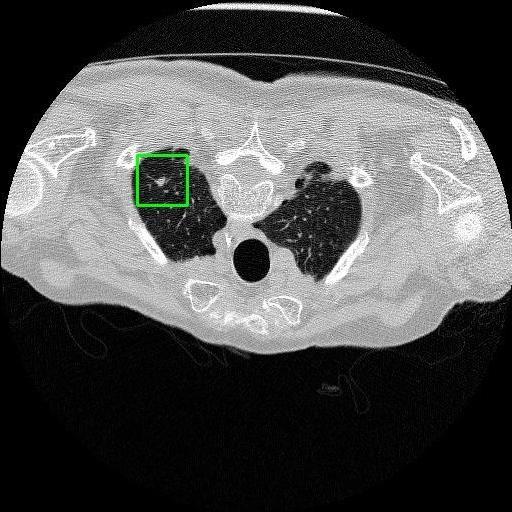

We developed an AI-based system using deep learning models for analyzing lung CT scans to detect and classify pulmonary nodules. We chose the YOLOv11 architecture for its enhanced object detection capability and adapted it specifically for medical imaging, incorporating pixel-level precision and severity classification.

Classification into three severity levels with colored bounding boxes.

Successfully built and deployed an AI model (YOLOv11) capable of detecting lung nodules in CT scans with high accuracy and real-time performance.

Designed a severity classification system that categorizes nodules into null, moderate, and severe using colored bounding boxes, assisting in rapid clinical decision-making.